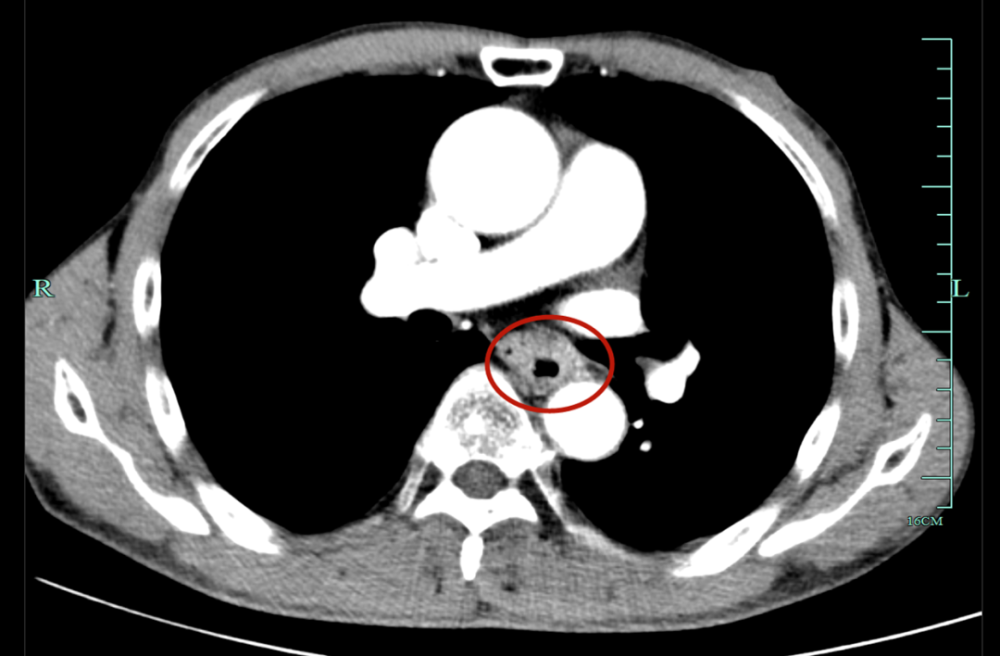

ct检查提示:c6-7水平食管内见线状高密度,长度约3cm,似见穿透外膜,与

考虑食管异物可能,急查颈部ct结果提示食管上段异物影,且穿透食道管壁